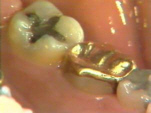

Ésta es la apariencia de la región después

de 6 meses. El margen gingival se ha retraído y al sondaje

no evidencia sangrado. La división de las raíces en el molar está

expuesta y crea problemas especiales para el paciente en los

procedimientos de higiene dental diaria.